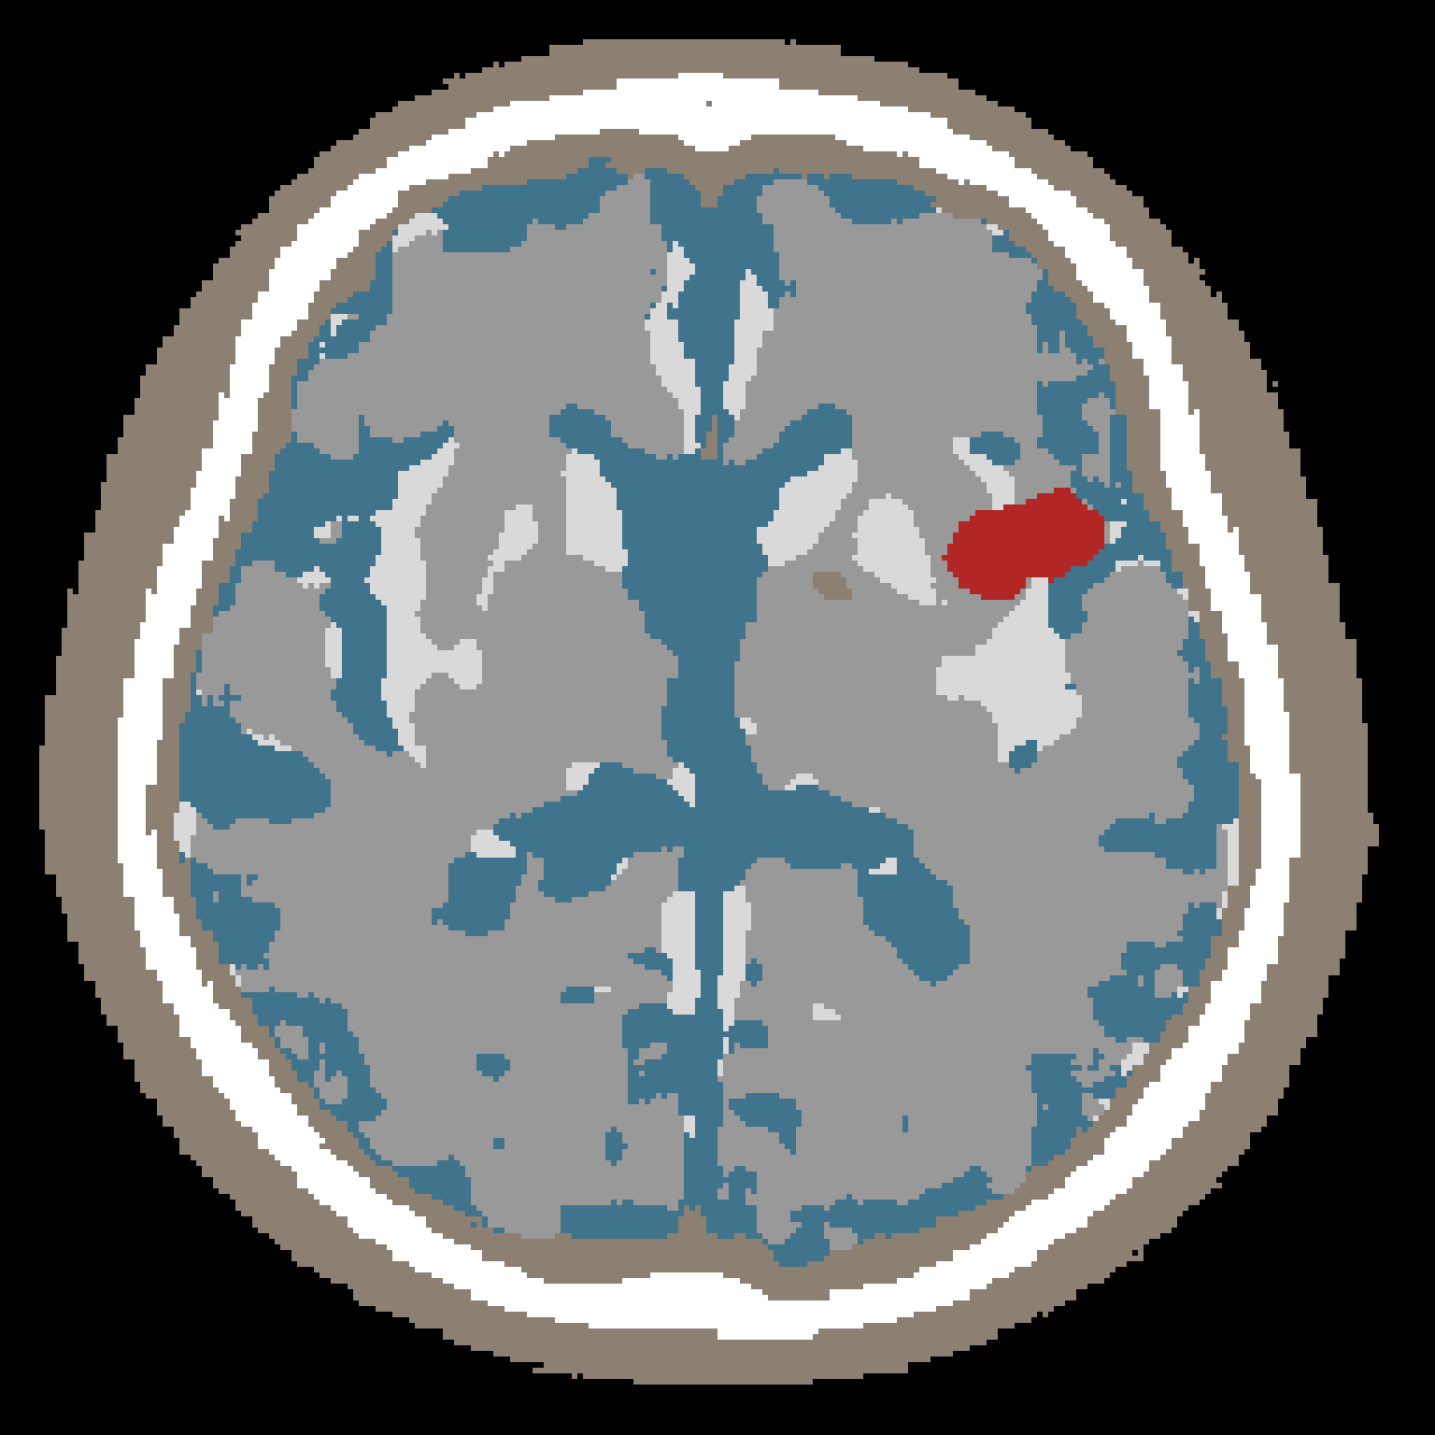

To obtain non-lesion tissue labels, we applied an automatic brain tissue segmentation pipeline based on CTseg222https://github.com/WCHN/CTseg, a deep learning framework for multi-class tissue segmentation in non-contrast CT. In brief, CTseg performs dense pixel-wise classification using a fully convolutional neural network that extracts hierarchical features from CT slices and produces anatomically consistent maps of major tissue compartments [8]. We used CTseg to segment background, cerebrospinal fluid (CSF), skull/bone, and brain parenchyma-related tissues, as show in Figure 2. These outputs served as the baseline tissue segmentation for each slice.

Refer to caption

Figure 2: Example of multi-class tissue segmentation on a representative NCCT slice. CTseg was used to automatically segment normal tissue classes, whereas ischemic infarct regions correspond to manual annotations provided by expert annotators.

All masks were resized to a fixed spatial resolution of 256×256256\times 256 pixels using nearest-neighbor interpolation, preserving discrete boundaries and preventing label mixing. Each mask was converted from a single-channel label map into a one-hot tensor X{0,1}C×H×WX\in\{0,1\}^{C\times H\times W} to enable categorical reconstruction losses during training. Color palettes were used exclusively for the visualization of qualitative results (Figure 2; all training was performed in label space.